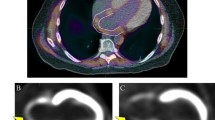

This study aims to analyze the left ventricular function parameters, scar load, and hypertrophy in a mouse model of pressure-overload left ventricular (LV) hypertrophy over the course of 8 weeks using 2-deoxy-2-[18F]fluoro-D-glucose ([18F]FDG) micro-positron emission tomography (microPET) imaging.

LV hypertrophy was induced in C57BL/6 mice by transverse aortic constriction (TAC). Myocardial hypertrophy developed after 2–4 weeks. ECG-gated microPET scans with [18F]FDG were performed 4 and 8 weeks after surgery. The extent of fibrosis was measured by histopathologic analysis. LV function parameters and scar load were calculated using QGS®/QPS®. LV metabolic volume (LVMV) and percentage injected dose per gram were estimated by threshold-based analysis.

The fibrotic tissue volume increased significantly from 4 to 8 weeks after TAC (1.67 vs. 3.91 mm3; P = 0.044). There was a significant increase of the EDV (4 weeks: 54 ± 15 μl, 8 weeks: 79 ± 32 μl, P < 0.01) and LVMV (4 weeks: 222 ± 24 μl, 8 weeks: 276 ± 52 μl, P < 0.01) as well as a significant decrease of the LVEF (4 weeks: 56 ± 17 %, 8 weeks: 44 ± 20 %, P < 0.01). The increase of LVMV had a high predictive value regarding the amount of ex vivo measured fibrotic tissue (R = 0.905, P < 0.001). The myocardial metabolic defects increased within 4 weeks (P = 0.055) but only moderately correlated with the fibrosis volume (R = 0.502, P = 0.021). The increase in end-diastolic volume showed a positive correlation with the fibrosis at 8 weeks (R = 0.763, P = 0.017).

[18F]FDG-PET is applicable for serial in vivo monitoring of the TAC mouse model. Myocardial hypertrophy, the dilation of the left ventricle, and the decrease in LVEF could be reliably quantified over time, as well as the developing localized scar. The increase in volume over time is predictive of a high fibrosis load.